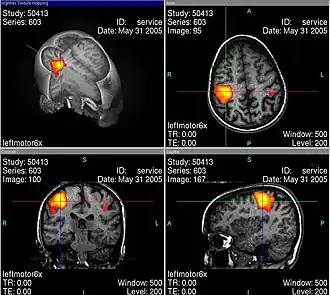

Les images d'IRMf bien connues (voir par exemple ci-contre) sont toujours interprétées selon des modèles qui en permettent la lisibilité. Pendant une tâche cognitive, le cerveau est constamment actif dans un grand volume, et il faut trier pour obtenir des images significatives, dépourvues de toutes les activités apparemment secondaires. Ce genre de tri se fait avec une méthode de soustraction : par exemple si l'on s'intéresse à une tâche cognitive K, alors on mesure l'activité du cerveau dans une situation S1 dans laquelle K est accomplie. Ensuite, on mesure l’activité dans une situation de contrôle S2 qui ressemble à S1, mais qui n'a a priori rien à voir avec la tâche K. Finalement, on soustrait les activités mesurées dans S2 de celles mesurées dans S1, pour voir les activités corrélées avec la tâche K de façon spécifique. Illes souligne qu'il faut toujours garder en tête ces aspects interprétatifs, ce qui peut facilement passer inaperçu devant un tribunal, parce que les juristes n'ont probablement aucune compétence en neurologie.

L’usage de l’imagerie cérébrale dans des programmes de recherche en neuropsychologie nécessite de bien maîtriser tous les artefacts et biais statistiques possibles, par exemple lors de l’IRMf en faisant des moyennes spatiales, temporelles et interindividuelles. La base de cet examen est de déterminer des corrélations entre certaines tâches mentales (langage, attention, mémoire…) et des activations spécifiques de zones du cerveau[33].

Les activités électriques du cerveau conduisent à des variations de tension électrique à la surface de la tête, que l'on peut enregistrer avec des appareils convenables. Les neurosciences cognitives actuelles reposent très largement sur le procédé d'imagerie par résonance magnétique fonctionnelle (IRMf). En même temps, ce genre de méthode soulève déjà une série de questions éthiques. Au moyen de l'IRMf, l'activité dans le cerveau peut être mesurée avec une bonne définition spatiale et temporelle. Cette technique conduit à des problèmes éthiques en particulier quand on trouve au moins grossièrement des corrélations entre l'activité neuronale et l'état conscient du sujet. Comment se comporter quand on sait par des méthodes neurologiques, et non par ce qu'elle en dit, qu'une personne pense à quelque chose ou le sent ?

En outre, les technologies correspondantes ne sont pas encore complètement sûres. Judy Illes et ses collègues du Neuroethics Imaging Group de l'université Stanford indiquent la force suggestive des images d'IRMf, qui cachent souvent des problèmes réels d'analyse des données[34].

Turhan Canli explique : « L'image d'un type d'activité basée sur une étude de mauvaise qualité ne peut pas être visuellement distinguée de celle d'une étude exemplaire. On doit être un habile spécialiste pour éventuellement remarquer la différence. C'est là que réside le grand danger d'abus des données d'imagerie auprès d'un public non éduqué, comme le jury d'une cour d'assises. Si l'on regarde les images, on peut facilement oublier qu'elles représentent des déductions statistiques et jamais une vérité absolue[35] ».